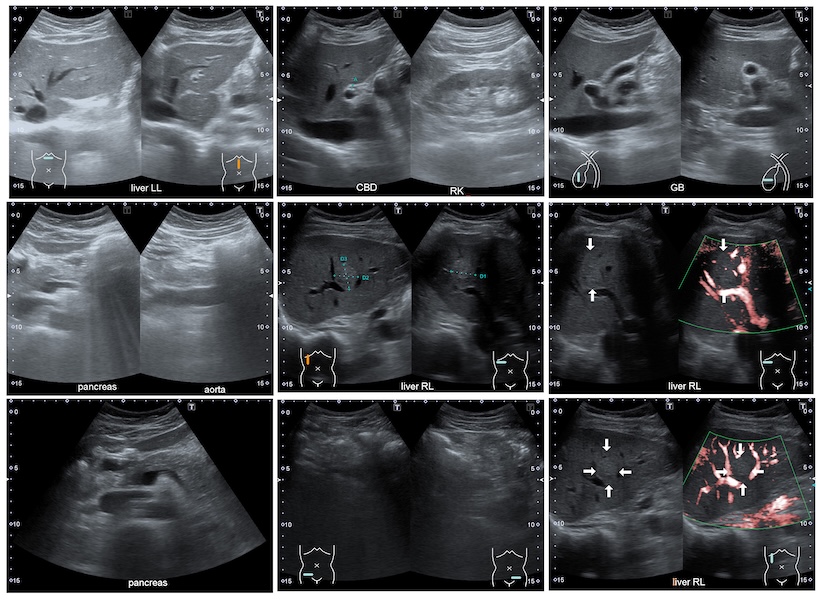

Your doctor may order an ultrasound test to look for gallstones, and/or another test called a HIDA scan to check the function of your gallbladder.